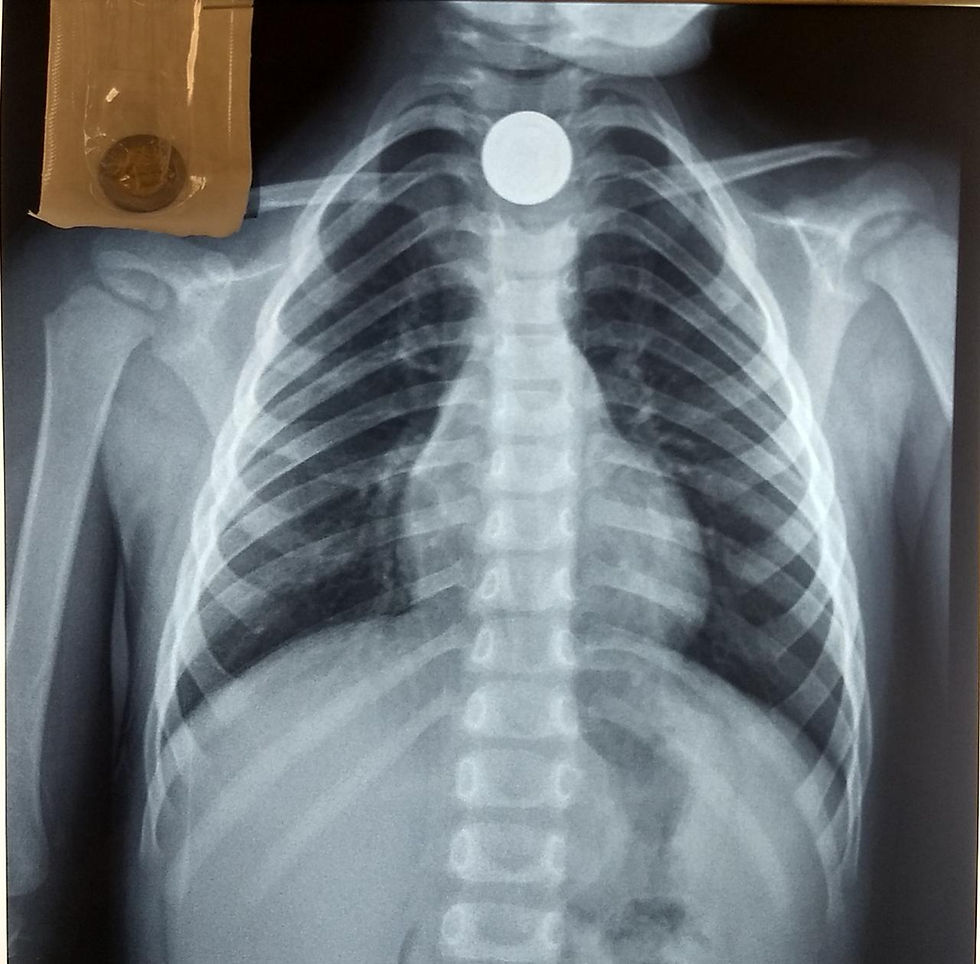

César Rodríguez González, gastroenterólogo pediatra adscrito al Hospital de Especialidades Pediátricas (HEP), señaló que el cuerpo extraño más frecuente son las monedas de un peso, que representan el 90 por ciento de estos casos.

“Es una emergencia muy frecuente, pues los niños son curiosos, traviesos y a veces suceden accidentes, con un susto o brinco pueden tragarse la moneda que queda en el primer tercio del tubo digestivo, el esófago”, mencionó.

“No tenemos una estadística exacta, pero por ejemplo la semana pasada sacamos una moneda, de cada 100 pacientes que llegan con un cuerpo extraño, más del 90 por ciento son monedas, de ellas, más de la mitad son de un peso, pues las nuevas de 50 centavos suelen pasar de largo al estómago y siguen su camino hasta ser defecadas por el intestino”, señaló.

“Hace cinco o siete años, una niña de esta ciudad se tragó una moneda, se le dio la atención médica pero no se la sacaron, a los seis meses todavía la tenía, pasó todo ese tiempo sin síntomas y luego tuvo problemas para deglutir, por lo que llegó a la sala de urgencias, le tomaron una placa de rayos X y encontraron la moneda”, dijo, esto puede desencadenar consecuencias a largo plazo.